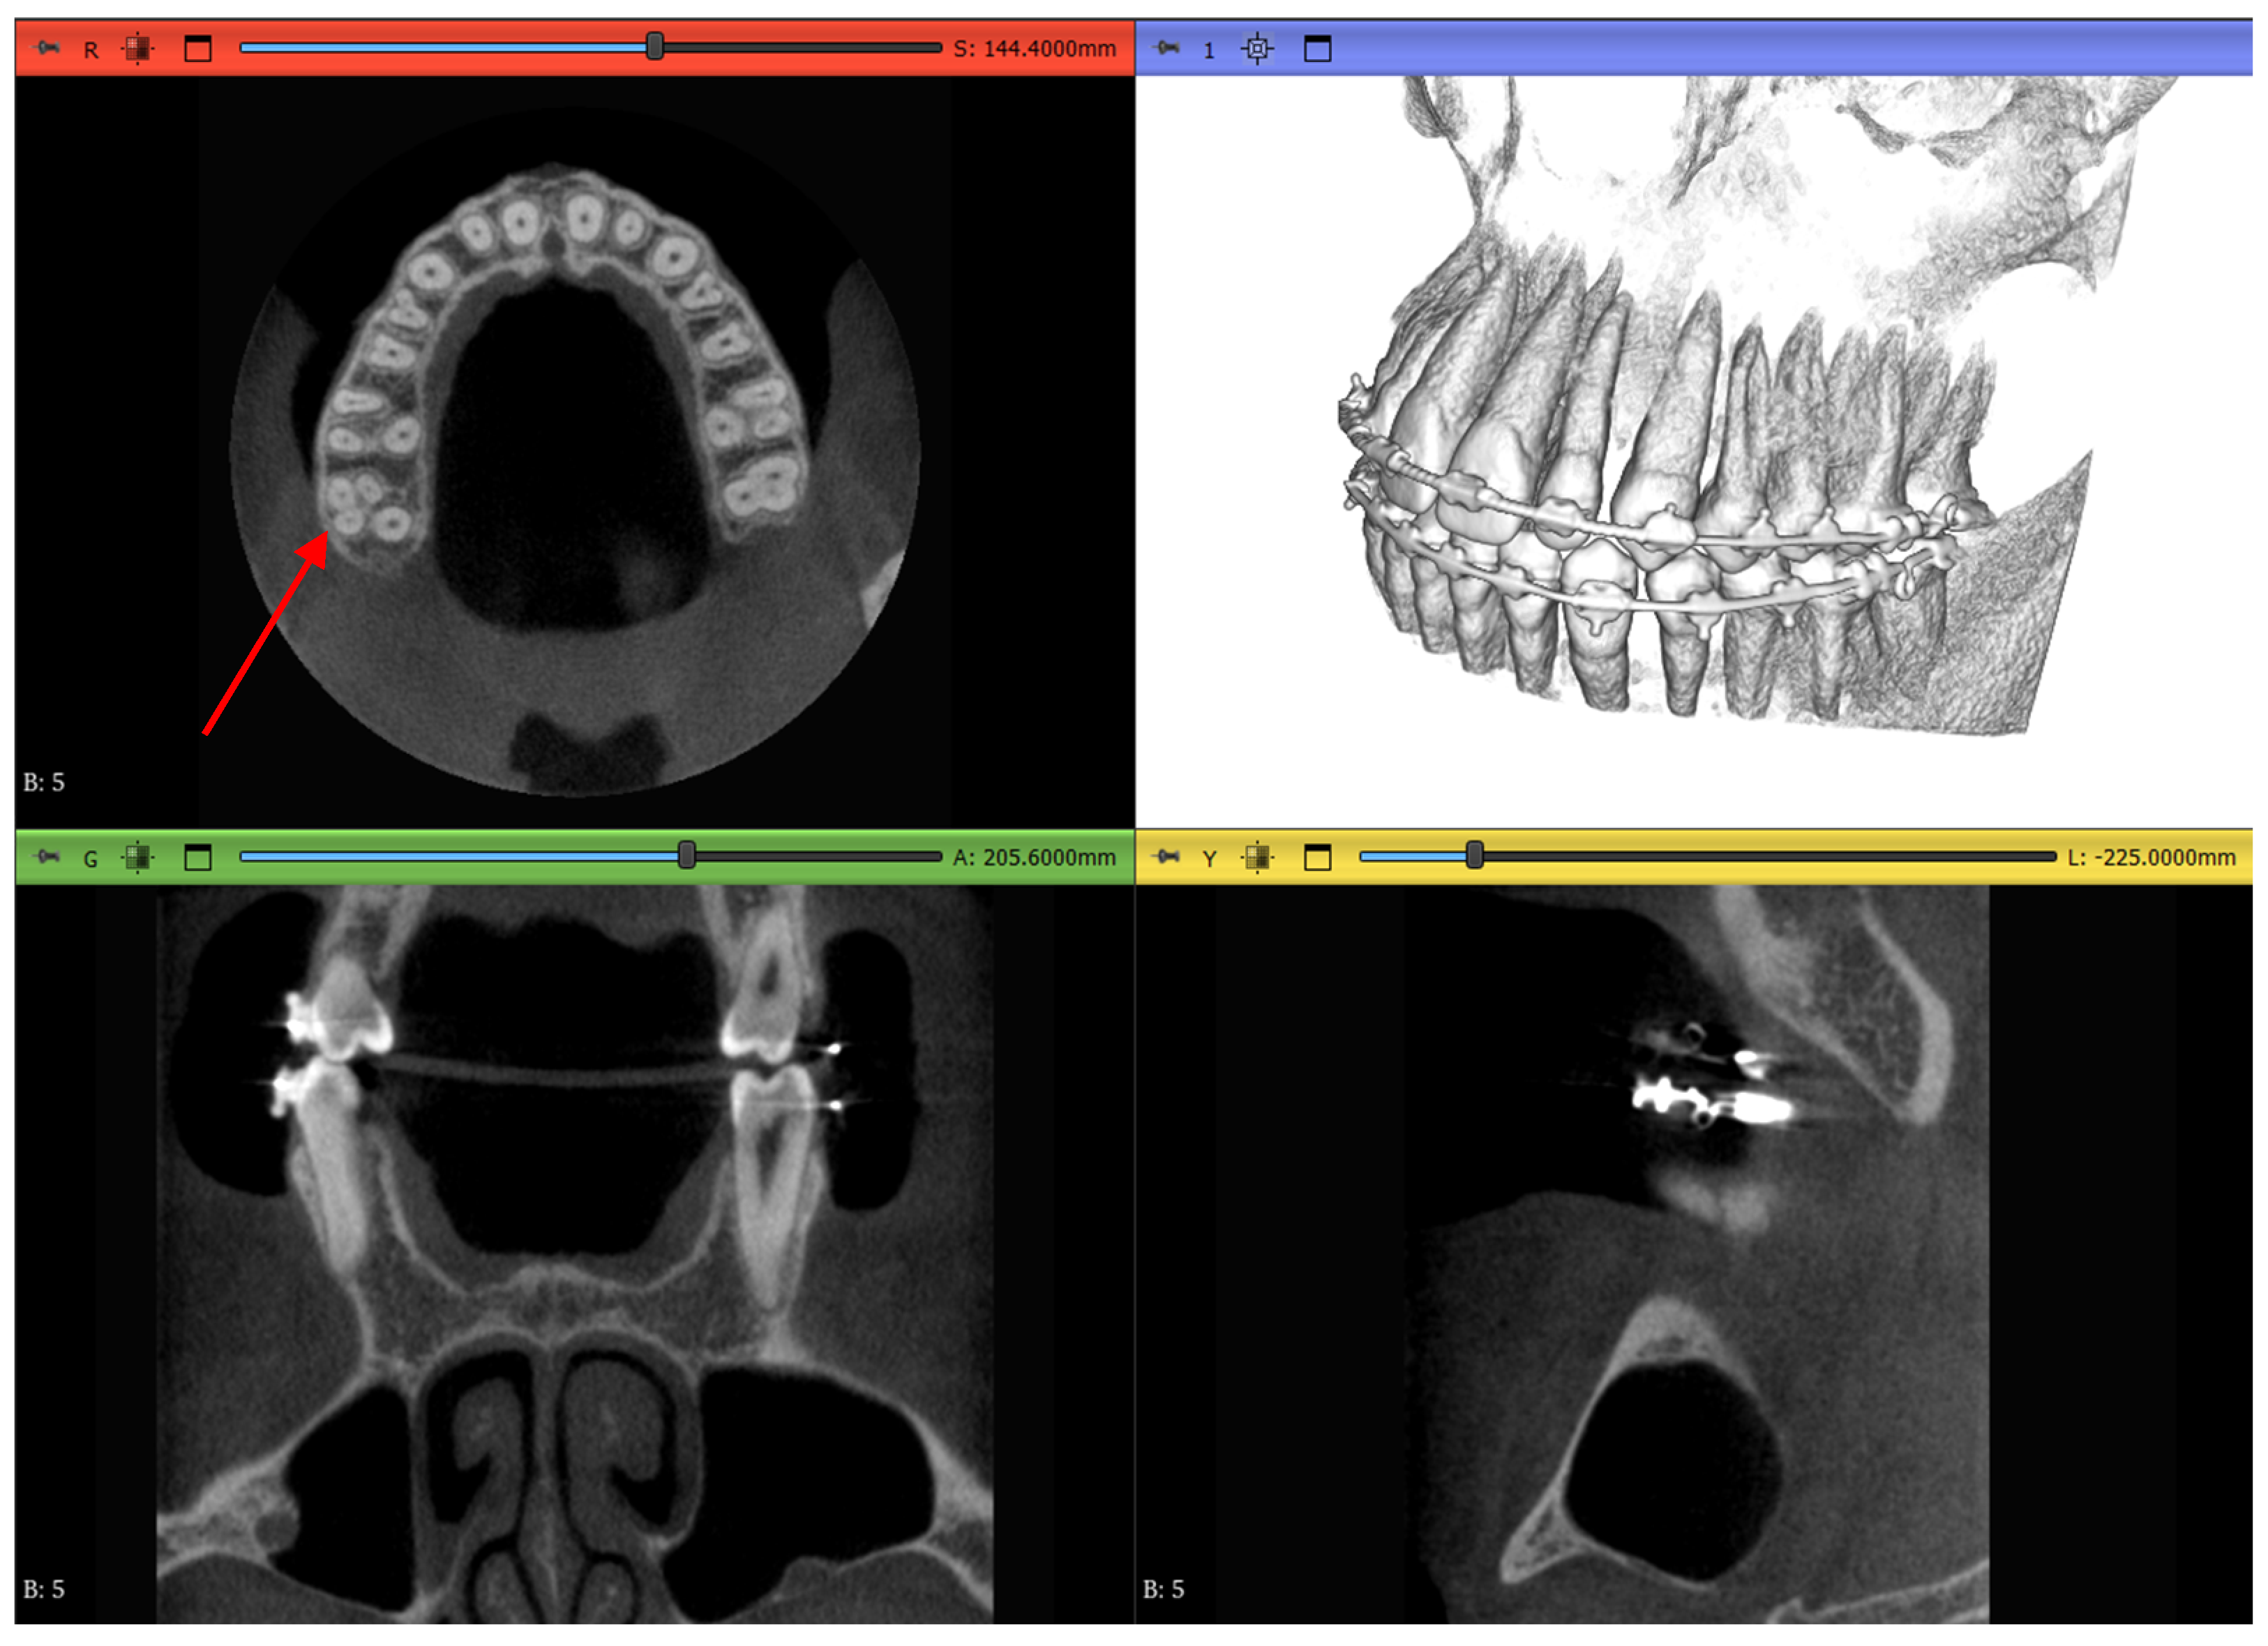

Dataset 3 presents the most challenging obstacle to the workflows, as it includes braces, and the maxillary second molar chosen has 4 roots instead of the more common 3-root configuration, as shown in Figure 6 by the red arrow.

Figure 6.

Dataset 3 of the study with a red arrow pointing to the 4-rooted maxillary second molar.